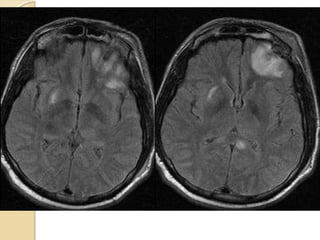

Axial FLAIR imagesAxial FLAIR images

AXIAL FLAIRAXIAL FLAIR